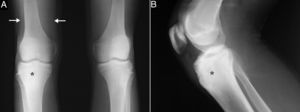

A 15-year-old boy presented with an 8-month history of mechanical pain in right knee. It would be intermittent at first and later become continuous, making it difficult for him to walk, and swelling was observed in that area. The treatment consisted of nonsteroidal anti-inflammatory drugs (NSAID), initially ibuprofen, which was replaced by diclofenac, but there was no improvement. He had no history of injury, fever or constitutional symptoms, or manifestations affecting any other peripheral or axial joint or enthesitis. He had been diagnosed with guttate psoriasis at the age of 10 years, with occasional episodes until he was 13, and was treated with topical glucocorticoids; however, he had no family history of psoriasis, psoriatic arthritis, ankylosing spondylitis or inflammatory bowel disease. Physical examination revealed muscle atrophy in distal thigh and swelling in right infrapatellar region, which was warm, and he had a limitation in last few degrees of flexion, but with no signs of joint effusion. The results of laboratory tests, including biochemical analyses, complete blood count and acute-phase reactants (erythrocyte sedimentation rate 6mm/h, C-reactive protein 2.31mg/dL) were normal. Human leukocyte antigen (HLA) typing revealed the presence of Cw6, DR4 and DQ8 haplotypes, but not B27, and the patient was negative for rheumatoid factor and antinuclear antibodies. Plain radiography of the knees showed a sclerotic area in the upper third of right tibia (Fig. 1A and B), which, according to computed tomography (CT), corresponded to an osteolytic lesion measuring 5mm in diameter in anterior tibial tuberosity, with a “nidus” formed by an ossified matrix, compatible with OO (Fig. 2B and C), with extensive sclerosis of the medullary bone and a solid periosteal reaction in the adjacent cortical bone. Magnetic resonance revealed intense contrast uptake in and around the lesion, as well as in the surrounding bone edema and the Hoffa fat pad (Fig. 2C and D). Bone scintigraphy disclosed hyperemia and a focal increase in the osteogenic response in the proximal epiphysis of right tibia, with no other significant changes. The patient underwent CT-guided radiofrequency ablation, and the pain disappeared a few days after the procedure, and he recovered complete mobility 1 month later, although he had mild persistent muscle atrophy.